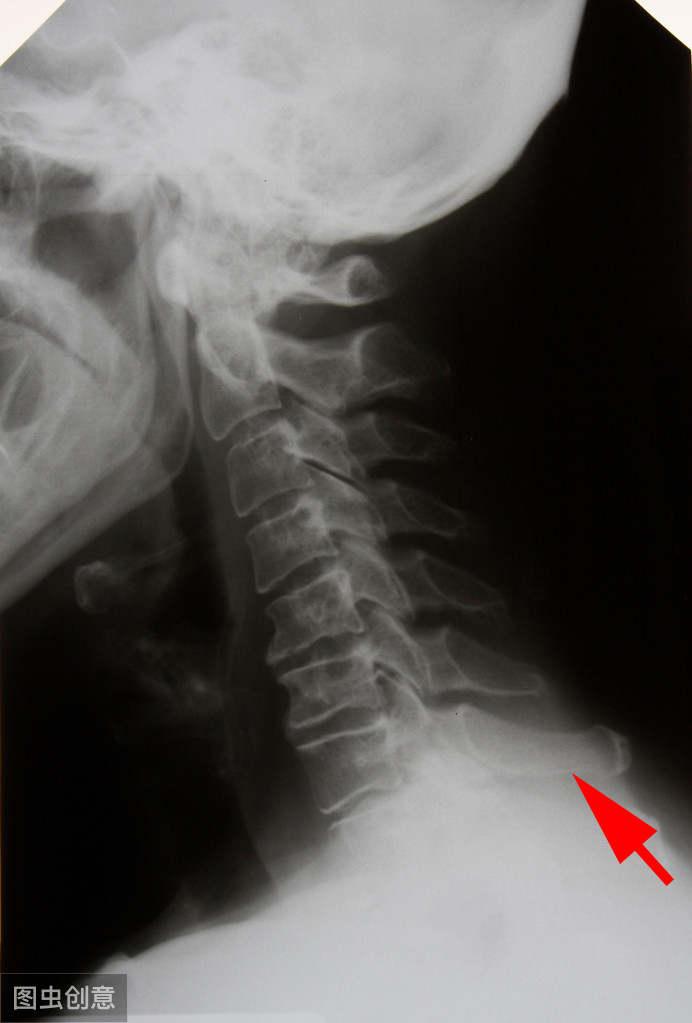

人的颈椎一共有七节,正常人的第七颈椎,它的后面本来就是凸起的。第七颈椎是颈椎的最后一节椎体,它伸向后方的棘突很长 ,由于其棘突很长,末端不分叉而呈结节状,隆突于皮下,而被称为隆椎 。它随着颈部的转动而转动,在人低头时看到和摸到颈部最高突起的部位,就是第七颈椎,第七颈椎其余的结构和其他颈椎是一样的(颈3-6椎体)。

颈七椎体是颈椎的最后一节椎体,它后方的棘突很长(红箭头所示)